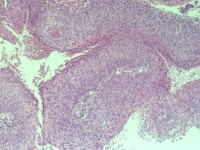

CINⅢ还是乳头状癌?

性别

女

年龄

73岁

临床诊断

宫颈癌

一般病史

阴道出血,宫颈口见菜花样组织

标本名称

宫颈组织

大体所见

1.5*1*0.5cm灰红碎组织

直接报鳞癌,手术后再定亚型(乳头状?疣性?浸润?),老头也要查查.

鳞状细胞癌

乳头状鳞癌。